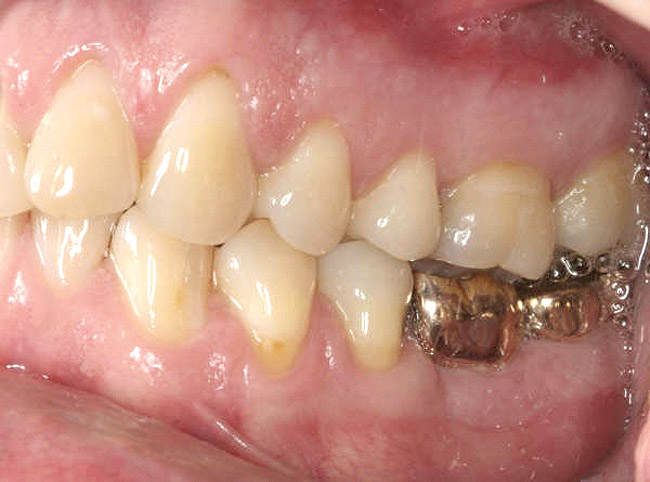

Figure 10a  Supra-eruption of the opposing arch, thus diminishing crown height space.

Figure 10a

Figure 10b  Supra-eruption of the opposing arch, thus diminishing crown height space.

Figure 10b